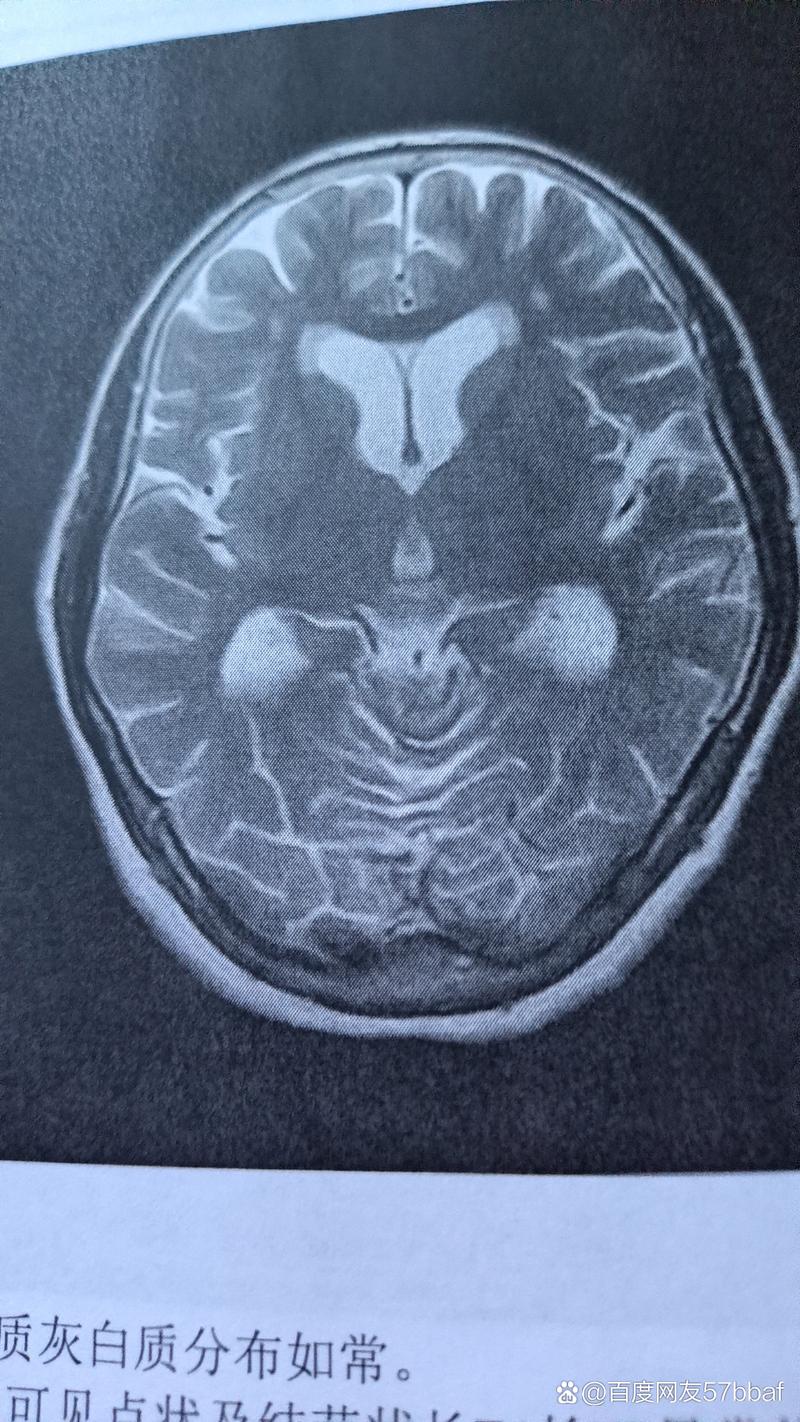

这是一个影像学(通常是CT或磁共振MRI)诊断报告,描述的是大脑中特定区域出现了多个由缺血引起的、已经坏死的脑组织。

- 解读:简单说,就是“脑梗塞”或“中风”留下的“疤痕”,这些坏死的脑组织无法再生,会形成小的腔隙,影像上看起来就是“病灶”。

在大脑两侧、靠近脑室的区域,出现了多个由于小血管堵塞或缺血导致脑组织坏死的病灶。

这种病灶在临床上有一个更常见的名称,叫做“腔隙性脑梗塞” (Lacunar Infarction)。